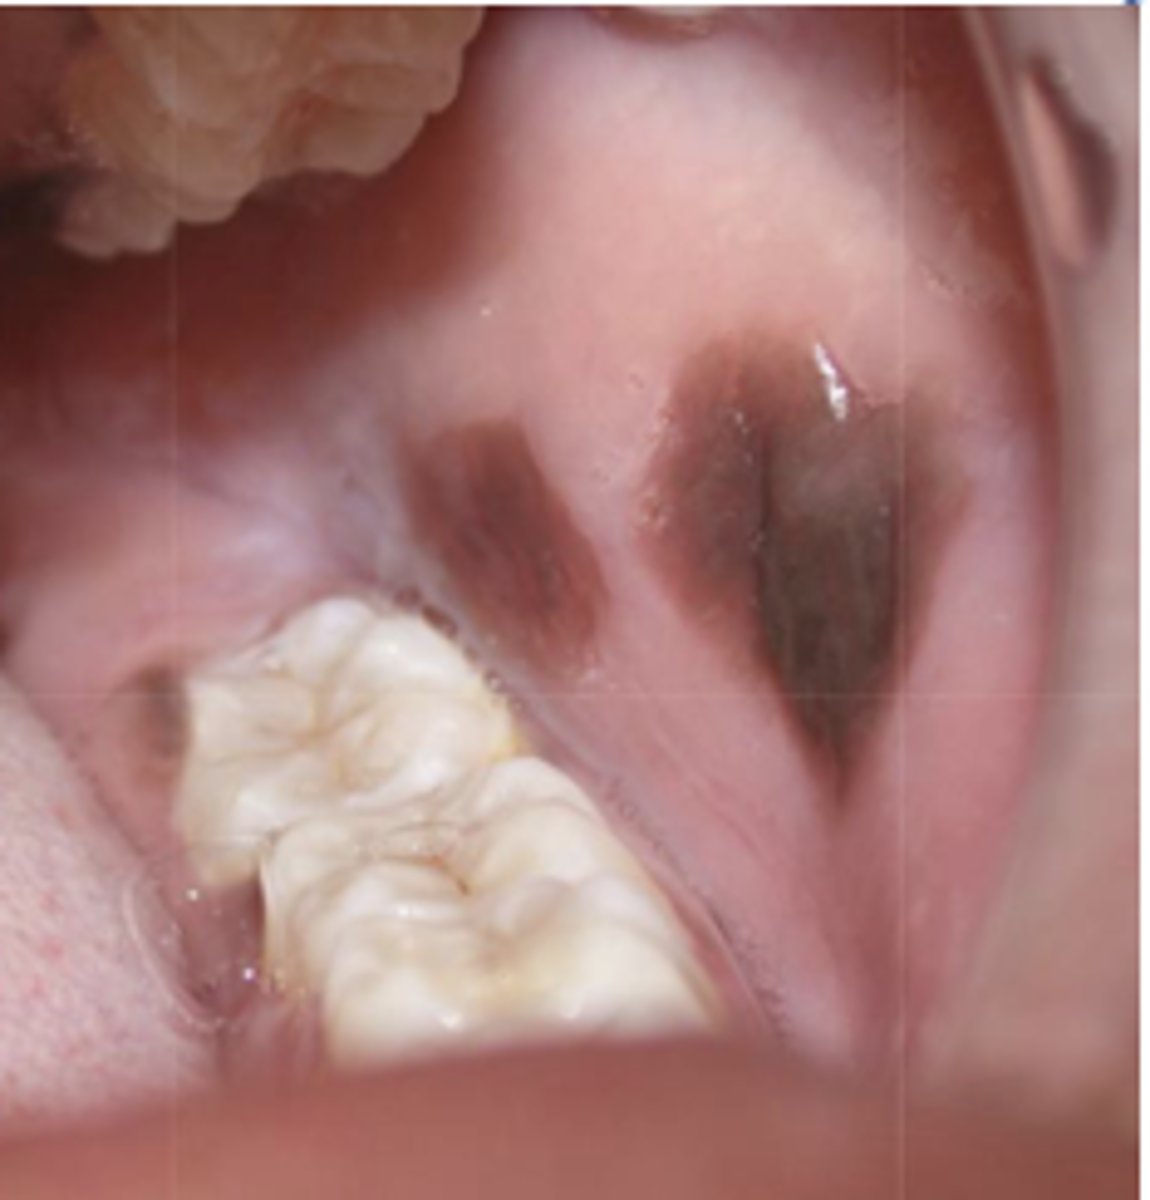

What type of pigmented lesion?

- Rare acquired pigmented lesion(s) of rapid onset

- Reactive?

- May reach several cm in size

oral melanoacanthosis (a.k.a. oral melanoacanthoma)

Oral Melanoacanthosis has a predilection for which ethnic group and which gender?

African American females

Oral Melanoacanthosis usually appears at which age?

3rd-4th decades

What is the differential diagnosis?

45 year-old African American female presented with this asymptomatic lesion for 2 months.

oral melanoacanthosis